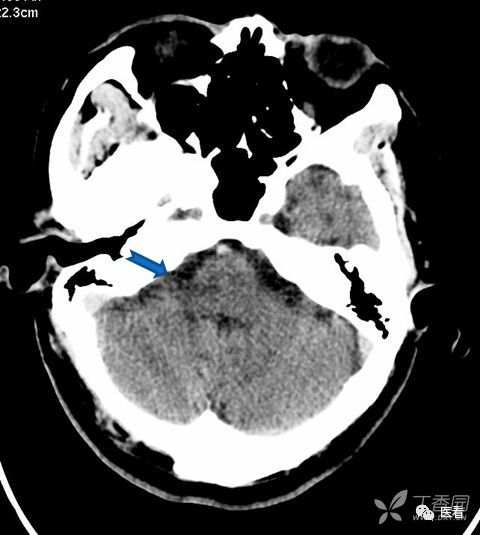

亨氏暗区

颅底(致密)骨产生的横行或放射状伪影,与设备性能也有关系

下图为16拍MSCT,伪影较轻。

此图为双排螺旋 CT图像, 伪影较16层及以上MSCT显著的多。